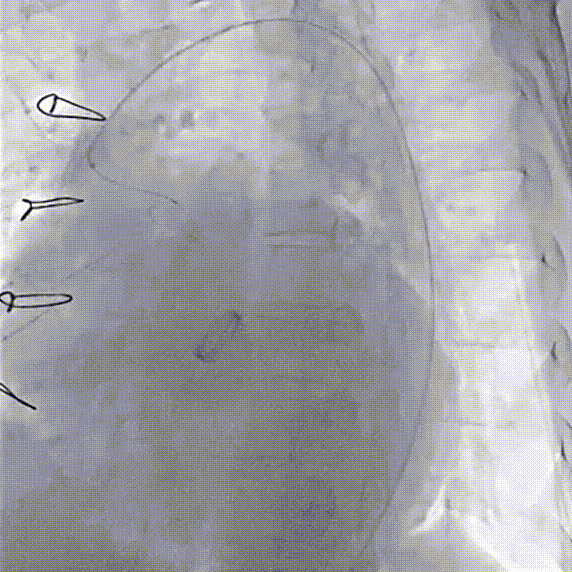

术前CT评估

术后CT评估